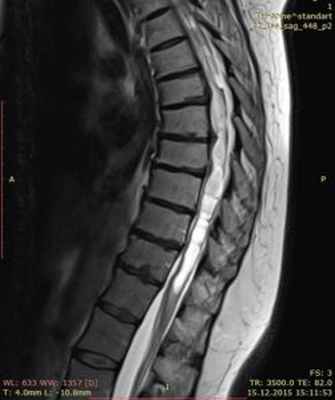

МРТ изображение (T2-взвешенное изображение) грудного отдела спинного мозга. Определяется сирингомиелия на фоне поствоспалительного арахноидита на уровне грудного отдела спинного мозга.